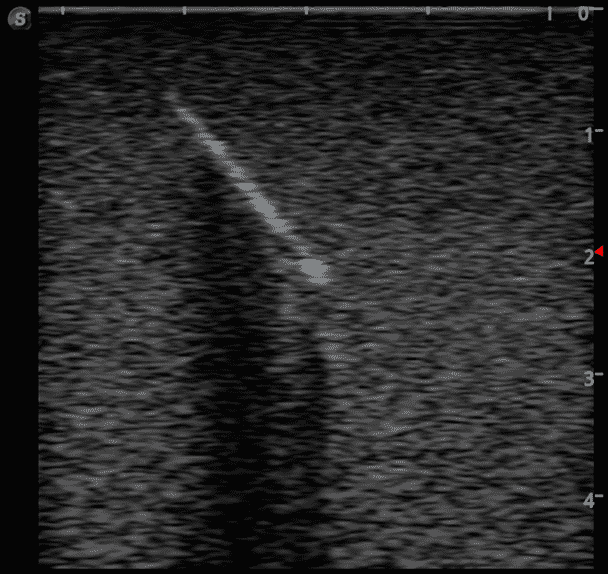

This training block is designed for training users in the techniques associated with ultrasound guided foreign body identification, targeting, and retrieval.

· High-quality ultrasound images

· Objects found in the human body including:

Glass shards

Wood splinter

Bullet

Plastic fragments

Metal fragments